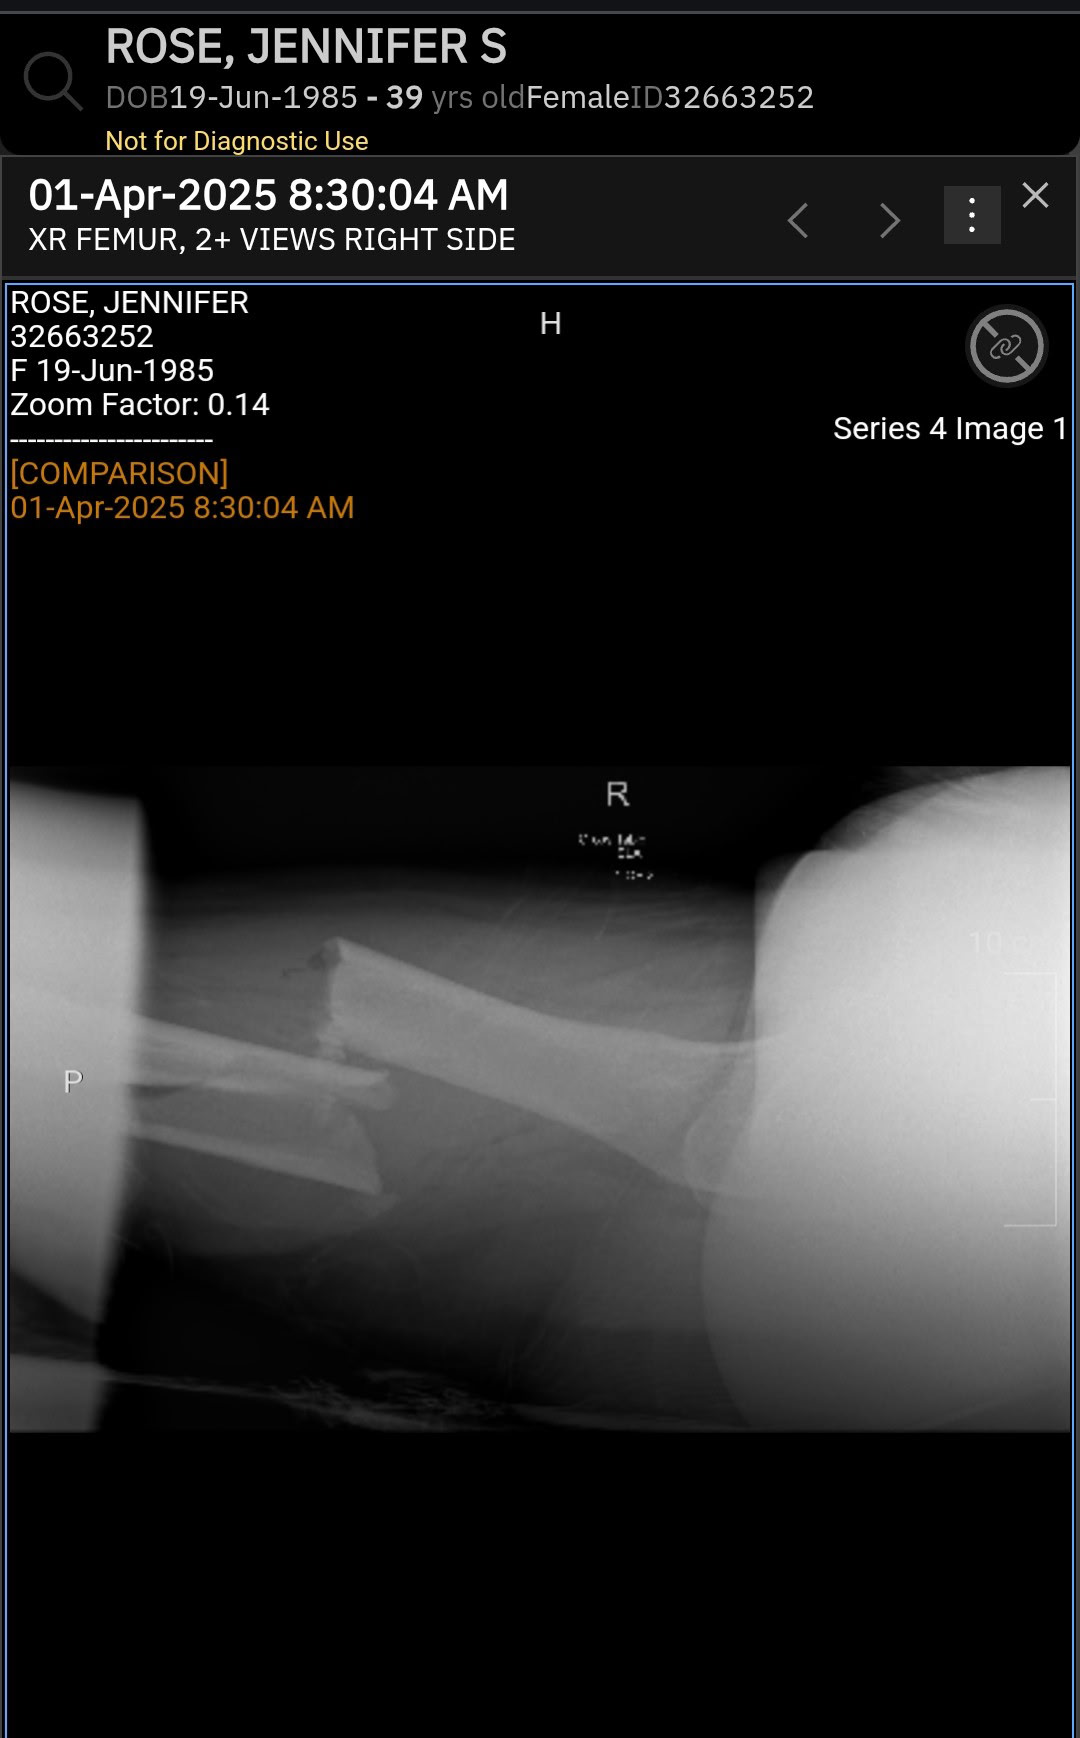

Unfortunately she was in an accident April 1. She was luckily saved by our firefighters using the jaws of life. She was then rushed into emergency surgery to save her leg and get a titanium femur put in. She stayed in the ICU for about a week, and the hospital as a whole the entire month of April.

All the muscles in her leg and body are adjusting to this new titanium rod. It causes incredible pressure on the stitches, muscles and tissues surrounding. Balance is not something you automatically have, and she sorely misses the ability to catch herself.